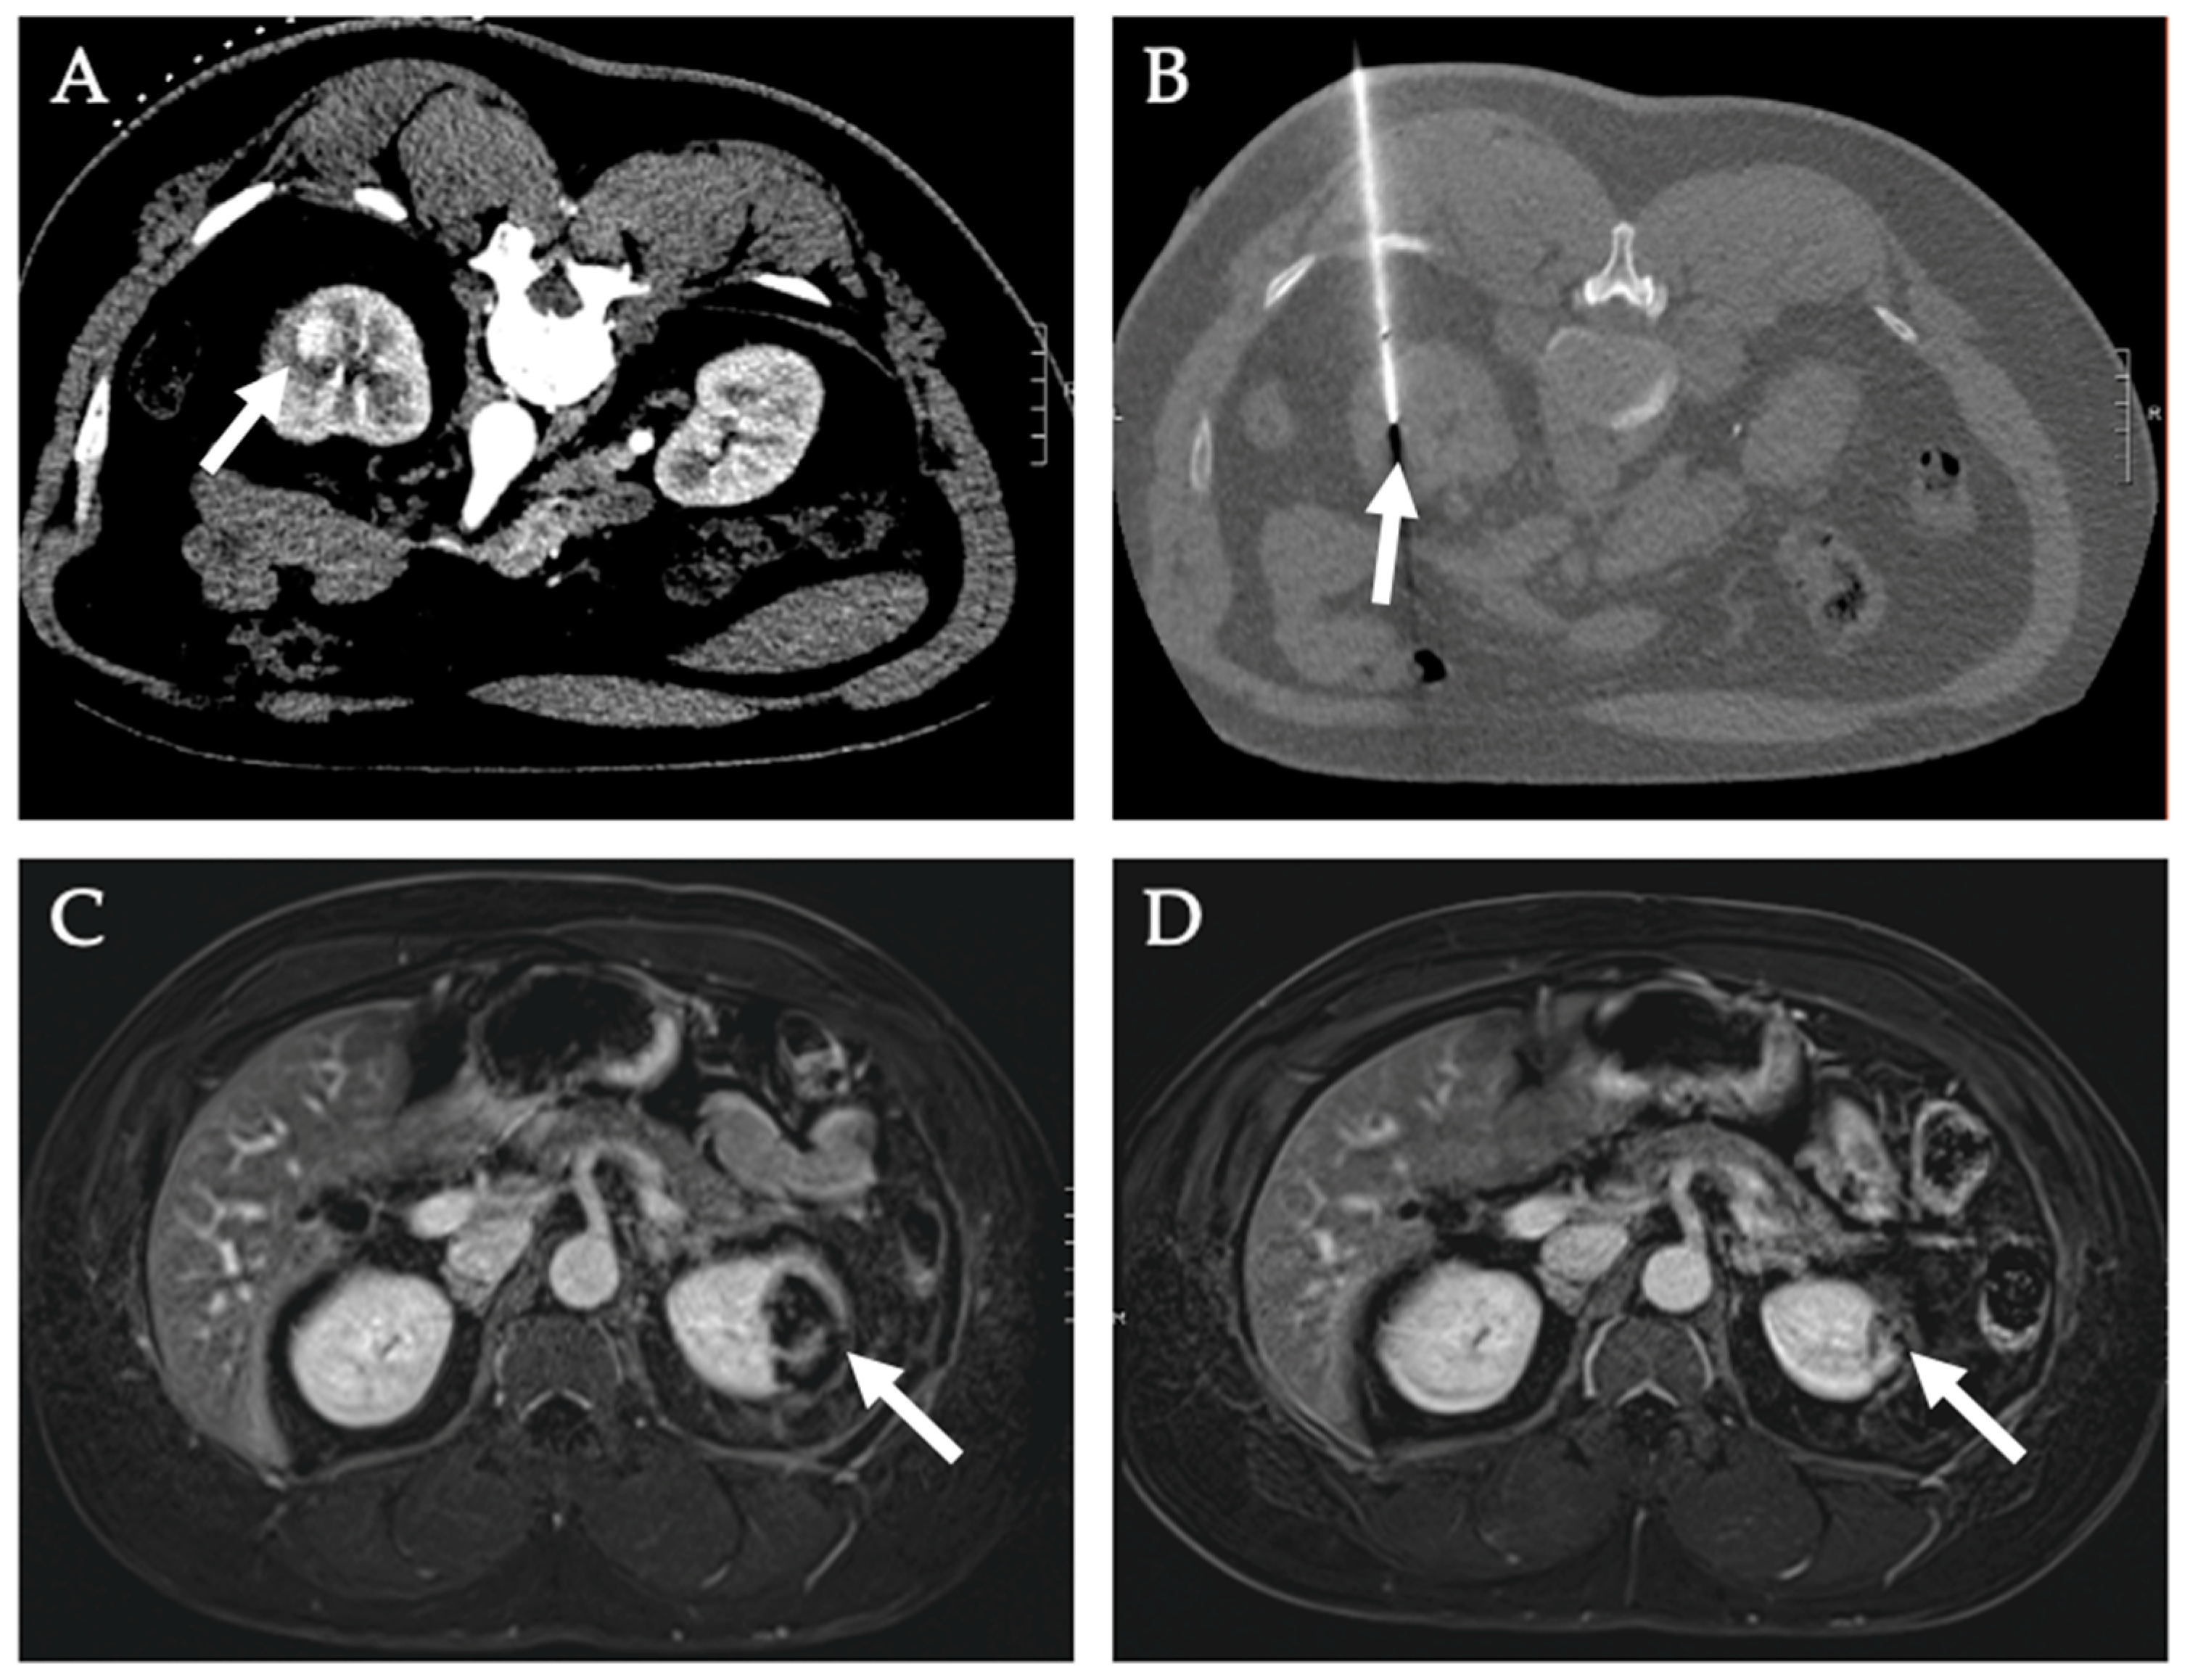

Diagnostics Free Full Text Image Guided Percutaneous Ablation For Primary And Metastatic Tumors